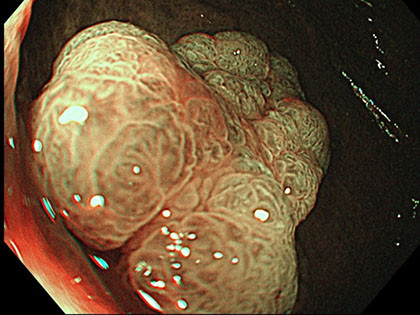

Entendemos por endoscopia digestiva a aquella prueba que permite la visualización directa de la mucosa intestinal (capa más interna del intestino) mediante un endoscopio.

Un endoscopio es un dispositivo que consiste en un tubo flexible (con longitudes y calibres variables en función del segmento de intestino a explorar),que incorpora un objetivo en su extremo final, acoplado a un cable de fibra óptica, el cual se prolonga a lo largo de toda la longitud del endoscopio y que se conecta a un procesador de vídeo, que muestra la imagen en un monitor.

De todos los métodos de los que se dispone en la actualidad para diagnosticar, la endoscopia sigue siendo una técnica fundamental. La ventaja de la endoscopia frente a otras técnicas, reside en que permite observar de manera directa la mucosa, tomar muestras de tejido (biopsias) y realizar procedimientos terapéuticos, como son la polipectomía (procedimiento quirúrgico ambulatorio que permite la extracción de pólipos durante la endoscopia) o la dilatación de estenosis (reducción del diámetro interno del intestino).